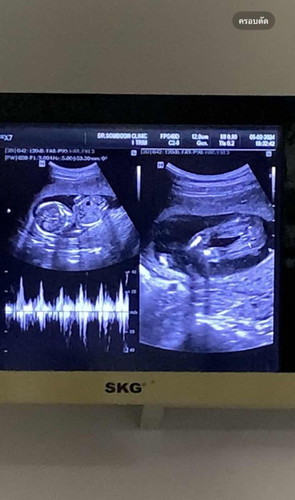

แม่ๆช่วยดูหน่อยค่ะ

น้องคือผู้หญิงใช่ไหมค่ะ แม่ๆ 🥰

ตอน อัลตร้าซาวด์ หมอไม่ได้บอกหรอคะว่าชายหรือหญิง น่าจะเป็นผู้หญิงค่ะ

ภาพไม่ค่อยชัดแต่ดูๆแล้วเห็นเป็นกลีบเลยค่ะ น้องน่าจะเป็นผู้หญิง

น่าจะผู้หญิงนะค่ะ แต่รอดูอีกทีก็ได้คะ บ้านนี้แบบนี้ ผู้ชายค่ะ

บ้านนี้ไม่ต้องรุนเลยน้องมีช้างน้อย😂🥰

เหมือน น้อง กระปู๊. เลยคะ😅😍